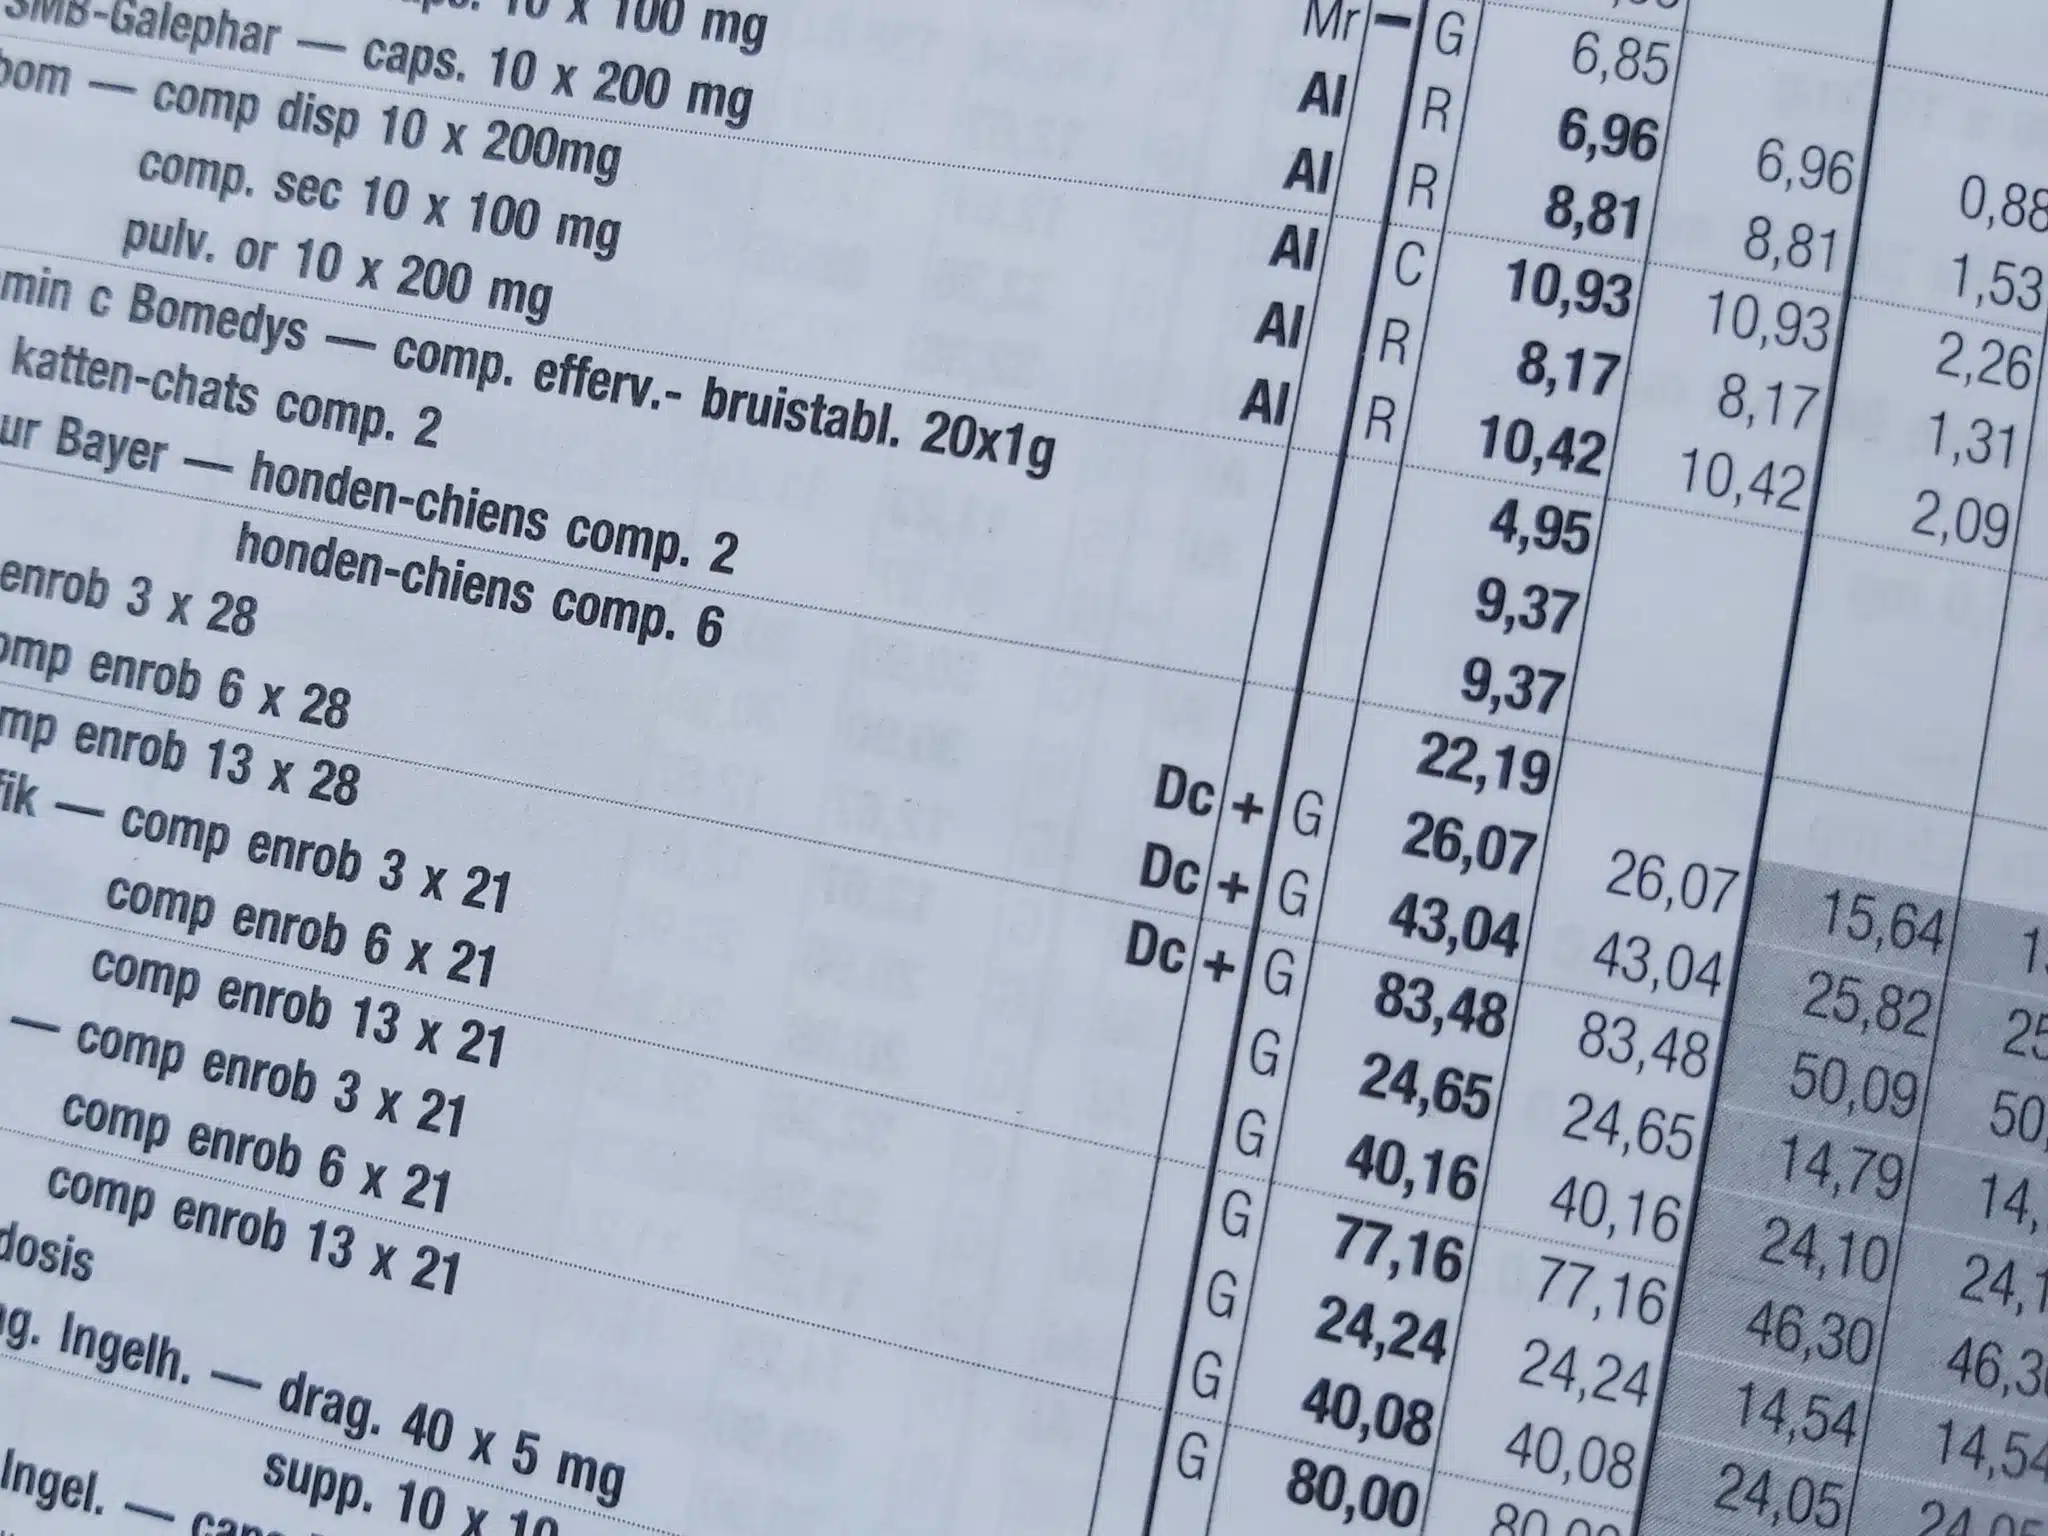

MODIFICATIONS DE PRIX ET REMBOURSEMENT AU 1ER OCTOBRE 2022

1. Baisses de prix au 1er octobre 2022: cliquez ICI Source APB 21/09/2022 2. Listes officieuses des spécialités les « moins chères » : à consulter sur le site APB Voir la page du site APB: cliquez ICI 3. Modifications des modalités de remboursement de spécialités au 1er…